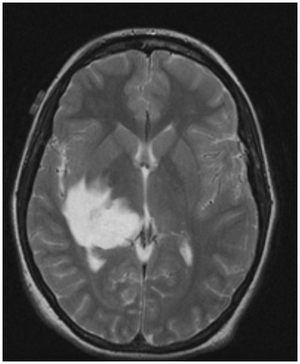

A 45 year old man with a 20-year diagnosis of HIV is brought to the physician by his partner after he notices cognitive changes in his partner. On neurological exam, the physician notes unilateral weakness. An MRI is ordered that reveals the following changes. What is the patient’s probably diagnosis given his presentation and underlying conditions?

Progressive multifocal leukoencephalopathy:

JC virus is a polyoma virus that causes a lytic infection of oligodendrocytes in immunocompromised persons.

70-80% of adults worldwide are seropositive for JC virus.

- Patients with compromised immune status especially AIDS patients are at risk for PML.